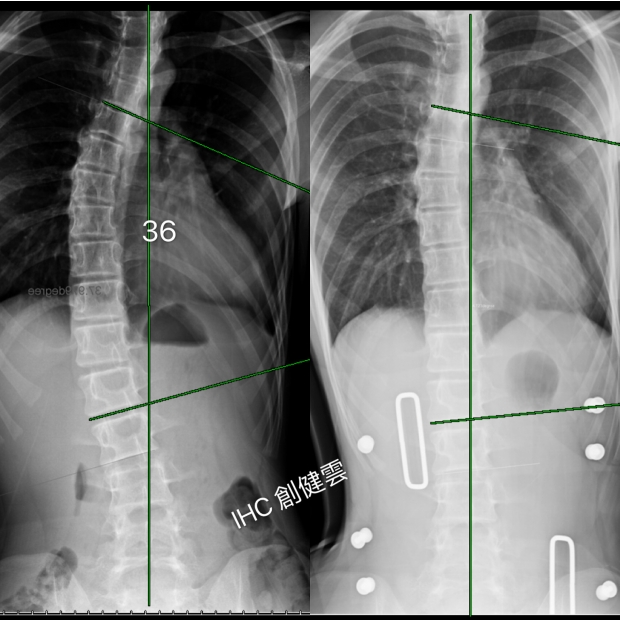

15歲S型脊椎側彎女孩

胸彎31度,腰彎35度